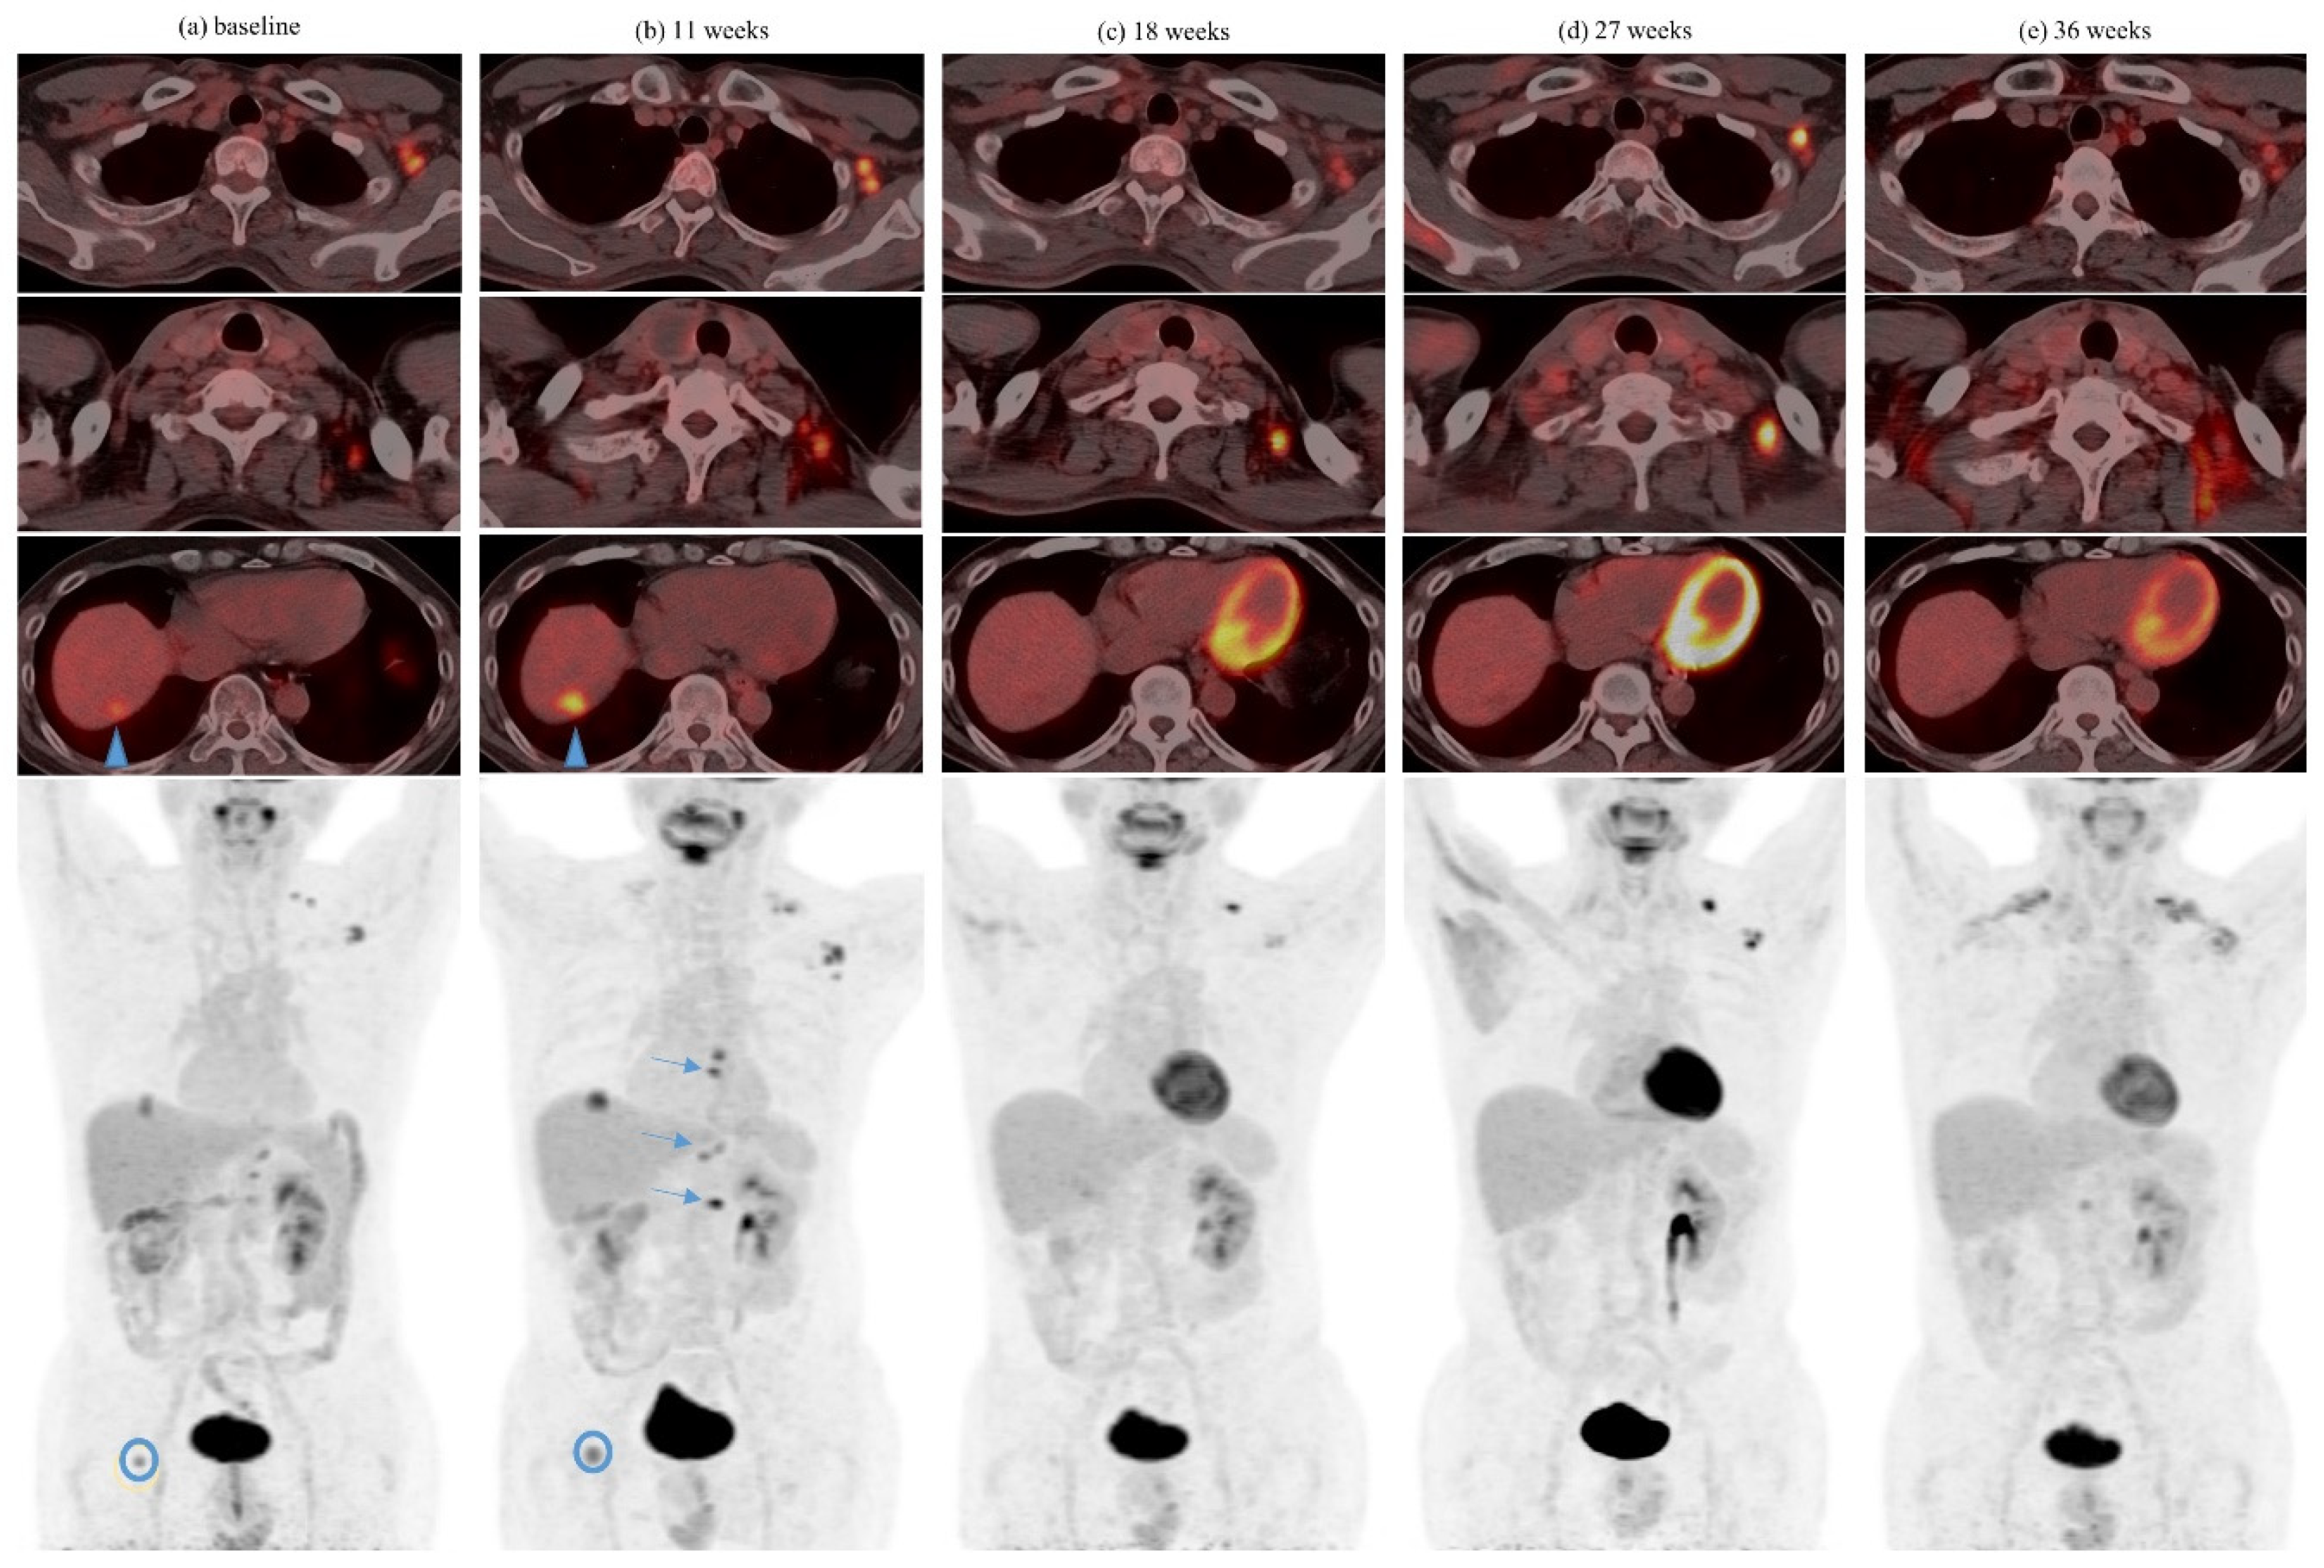

| Abscopal response | 4 | 26.7 | 5 | 16.1 | 9 | 19.6 |

| 1 | Ipilimumab + Nivolumab | 6 | 55Gy/20 | Yes | Lung | Lung, 1 | 3 | |

| 2 | Ipilimumab + Nivolumab | 6 | 25Gy/5 | 2 months after last dose of ICI | Femur, rib | Nephrectomy bed, 1 | 3 | CRS 3 after 2 fractions |

| 3 | Ipilimumab + Nivolumab | 10 14 | 36Gy/3 30Gy/5 | Yes Yes | Lung Adrenal | Lung, 2 Lung, 1 | 2 5 | 1 tumor with abscopal response after initial enlargement post SBRT 4 |

| 4 | Ipilimumab + Nivolumab | 12 | GKS 5 25Gy | 1 month after last dose of ICI | Brain (4 lesions) | Intramuscular, 1 | 2 | |

| 5 | Pembrolizumab | 3 6 | 8Gy/1 27Gy/3 | Yes Yes | Femur Pubic bone | Liver, several | 1 | Concurrent axitinib from prior line of treatment maintained |

| 6 | Nivolumab | 17 26 | 54Gy/3 42Gy/5 25Gy/5 | Yes Yes | Lung Lung | Lung, 2 Lung, 2 | 5 3 | Prior spontaneous regression and dissociated response after cytoreductive nephrectomy |

| 7 | Nivolumab | 6 7 7 | 50Gy/20 48Gy/3 48Gy/3 | Yes | Lung Lung Lung | Lung, 1 | 1 | |

| 8 | Nivolumab | 9 12 12 | 20Gy/5 24Gy/3 GKS 25Gy | Yes | Femur Iliac bone Brain (2 lesions) | Lung, several | 2 | |

| 9 | Nivolumab | 5 5 | 27Gy/3 24Gy/3 | Yes | Iliac bone Spine | Lung, several Kidney, 1 | 2 |